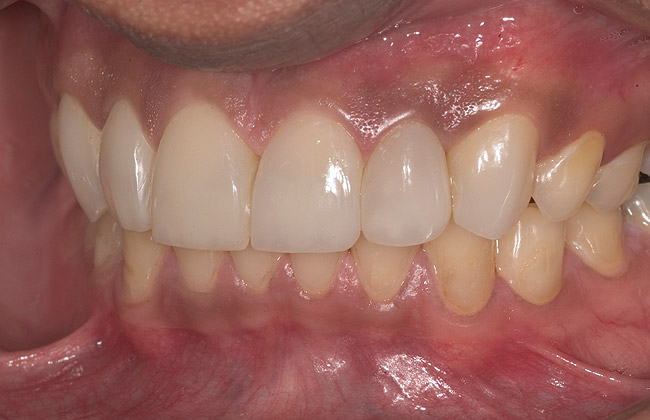

Figure 16  1:2 right lateral view; posteriors discluded in MIP.

Figure 16

Figure 17  1:2 left lateral view; posteriors discluded in MIP.

Figure 17